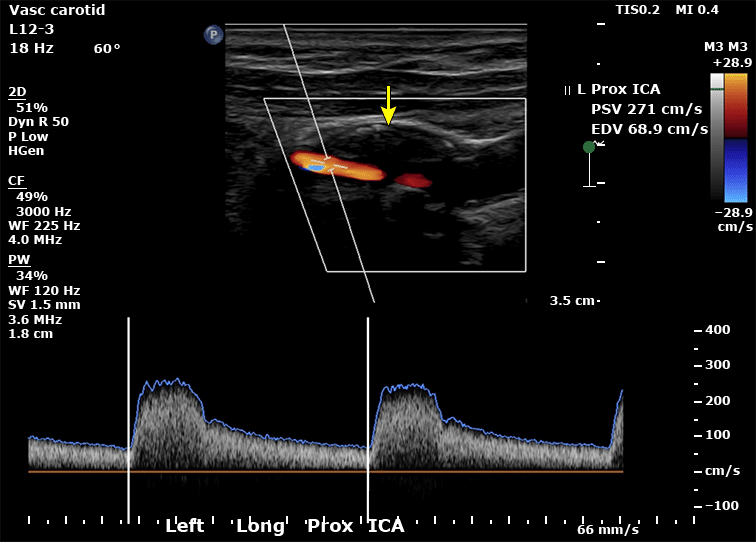

O Doppler de carótidas é o método inicial para avaliação de estenose carotídea, por ser acessível, não invasivo e com excelente acurácia para estenoses significativas. Ele permite avaliar a velocidade do fluxo sanguíneo, o grau de obstrução, além de aspectos da morfologia da placa aterosclerótica, como ulceração ou ecogenicidade.

A imagem abaixo mostra uma ultrassonografia duplex de carótidas evidenciando uma estenose de alto grau na carótida esquerda. Nota-se a presença de uma placa ecolucente de grandes dimensões na região do bulbo (indicada pela seta), associada a elevação das velocidades sistólica de pico e diastólica final (destacadas no canto superior direito).

No entanto, o Doppler tem limitações em casos de dissecção, onde pode não evidenciar o flap intimomedial. Também pode subestimar ou superestimar estenoses em vasos tortuosos ou com calcificações intensas.